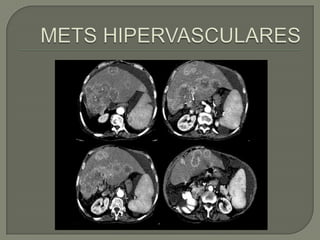

   Subgrupo de lesiones metástasis con importante

aportevascular.

   Similar aspecto a las hipovasculares, pero con

flujo importante a la valoración con Doppler color y

muchas veces son ecogénicas.

   Lostumores primarios con implantes hepáticos

hipervasculares mas frecuentes :

• Neuroendocrinos, sarcomas, células renales y melanoma.

• Neuroendocrinas: diferencial con hemangiomas

• Metástasis de melanomas: usualmente con sangrado

Subgrupo de lesiones metástasis con importante aportevascular.  Similar aspecto a las hipovasculares, pero con flujo importante a la valoración con Doppler color y muchas veces son ecogénicas.  Lostumores primarios con implantes hepáticos hipervasculares mas frecuentes : • Neuroendocrinos, sarcomas, células renales y melanoma. • Neuroendocrinas: diferencial con hemangiomas • Metástasis de melanomas: usualmente con sangrado